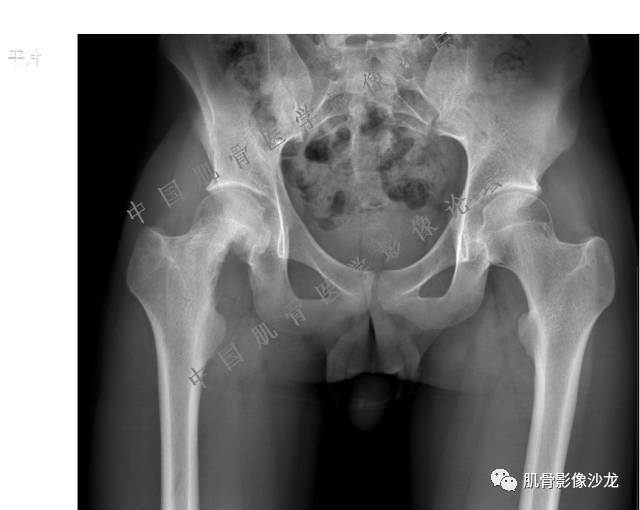

主诉:右髋及右膝部疼痛3月余

现病史:3月前打球时自觉右大腿肌肉拉伤后右髋及右膝部疼痛,自服“活血化瘀”类药物(具体不详)后自觉疼痛缓解,2月前打球时再次扭伤,右髋及右膝部疼痛明显,行走时疼痛加重,自服药物治疗,效果不佳,遂来诊。

Echo 20:23 我个人觉得,17岁男性,病灶发生在原干骺端区域,溶骨性骨质破坏,似有肿瘤骨,有软组织肿块形成,从常见病发生率来说,骨肉瘤还是要考虑的